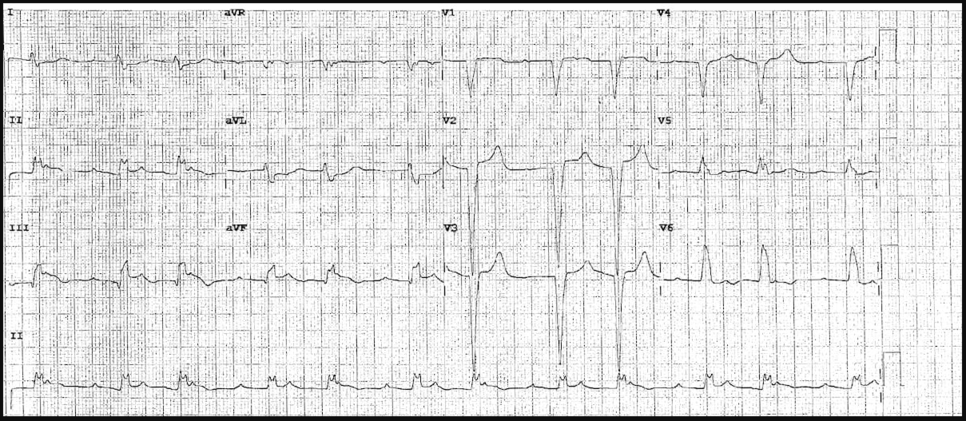

There is 1mm concordant ST elevation in aVL (= 5 points)

There is concordant ST depression in V2-5 (= Sgarbossa positive).

There is 1mm concordant ST elevation in II, III, aVF (= 5 points)

There is 1mm concordant ST elevation in aVL, V4-6 (= 5 points)

There is concordant ST depression in V1-3 (= Sgarbossa positive).

There is 1mm concordant ST elevation in aVL, V5-V6 (= 5 points)

There is 1mm concordant ST elevation in I, aVL, V5 (= 5 points)

There is concordant ST depression in V3 (= Sgarbossa positive).

There is 1mm concordant ST elevation in I, aVL (= 5 points)